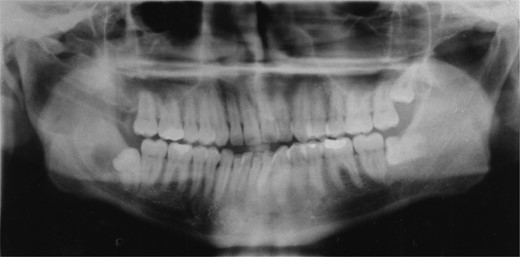

A 25-year-old man presented with a 2-month history of facial pain and limited mouth opening associated with a 3-week history of swelling of the right cheek. Radiographic analysis revealed a loculated, fluid-filled, well-demarcated lesion destroying and expanding the ascending ramus, extending out into the soft tissues, from the condyle down to the angle (Fig. 1).

A well-demarcated lesion extending out into the soft tissues from the ramus of the mandible.